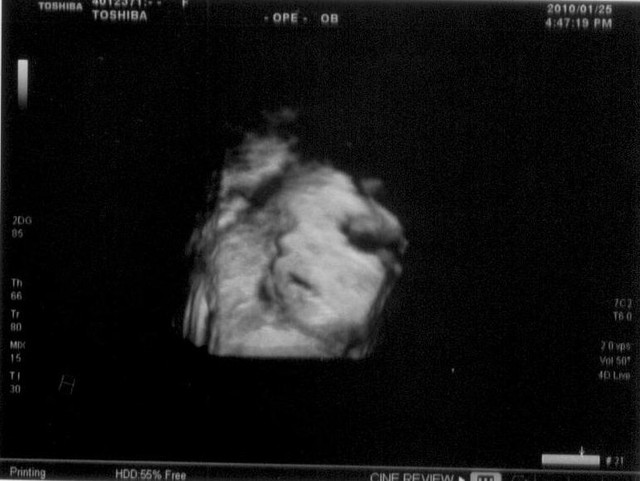

因為約好下午四點要照4D,一整個下午都很緊張,我也不知道我在緊張什麼…大概就是那種既期待又怕受傷害的心情。

三點五十分的時候,就把預備好的養樂多和PINKY拿出來吃,希望愛吃甜的小寶妞妞可以給點面子,讓她媽媽看看她的樣子。

一躺上TABLE,直覺不妙,因為小妞妞完全都不動耶…睡得可熟的呢!更糟糕的是,完全都看不到臉,原因不是她背對著我們,而是她把整個臉都靠在胎盤上,只看到一隻耳朵和臍帶

可是看得出手都一直擺在下巴附近,慶樺阿姨拍了我肚皮將近20分鐘,期間也一直跟她說話,但是小寶妞妞還是一點面子都不給,技術員只好叫我們下來走走動動個五分鐘,看她會不會翻個身轉個頭之類的。

再次躺到台上,妞妞已經醒來了,但是還是有一半的臉被胎盤遮到,看得到她一直嘴巴張合張合的,一開始以為在打哈欠,後來發現應該是在喝羊水吧!而且大姆哥不是放在下巴就是放在嘴唇上,這個愛吃的妞妞,折騰了將近45分鐘,才讓我們拍到這一張稍微清楚的照片。

本想再接再勵的繼續逗她,可是已經過了一個小時,還是照不到更清楚的角度,而且我的肚皮也開始硬了起來,小姐說:「好了…不要再拍了,萬一小孩衝出來就不好了」

所以我們又約了1/27(三)下午再繼續拍,希望小寶妞妞到時候不要這麼固執,怎麼叫都不理我…

拿著這張照片左瞧右瞧,還是看不出到底像誰?蠍子老爺為了看他女兒的玉照,下班後早早就衝回來~